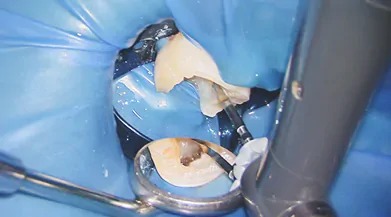

約20倍に拡大しながら治療を行えるため精密な治療が可能となります。裸眼では確認できない根の入り口や古い根管充填物など、活用方法は様々ですが、精密な治療ができるため、成功率を上げる事ができます。

1ラバーダム防湿

歯に薄いゴムのシートをかけ、周囲を消毒します。これによりお口の中の唾液が治療中の根管内に入らないようにし、無菌的な治療を行います。(お口の中は細菌だらけなんです・・・)根の治療においてこのラバーダムは一番大事な処置です。これをする事によって文献上で成功率が上がるのが示されています。

2むし歯除去

痛みの原因となっているむし歯を取り除きます。